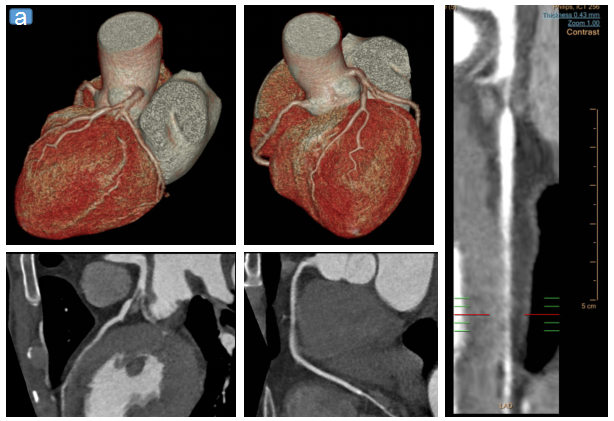

注:图a为冠状CTA图像;图b为冠状DSA图像